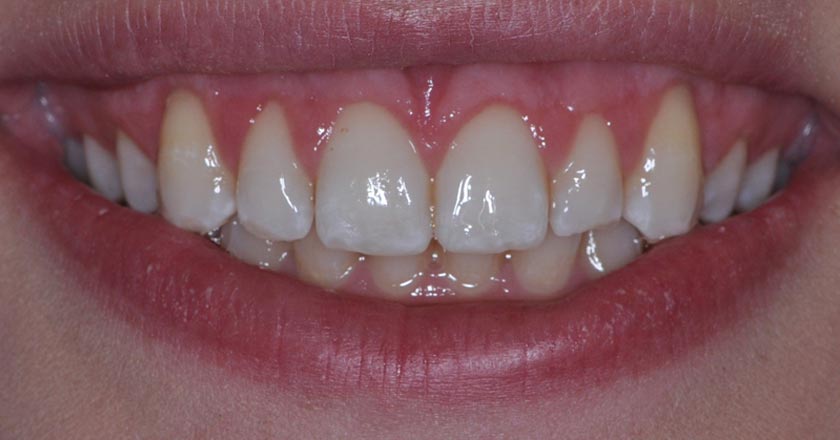

Gummy Smile - Before And After

Gummy smile correction – before treatment 1

Gummy smile correction – after treatment 1